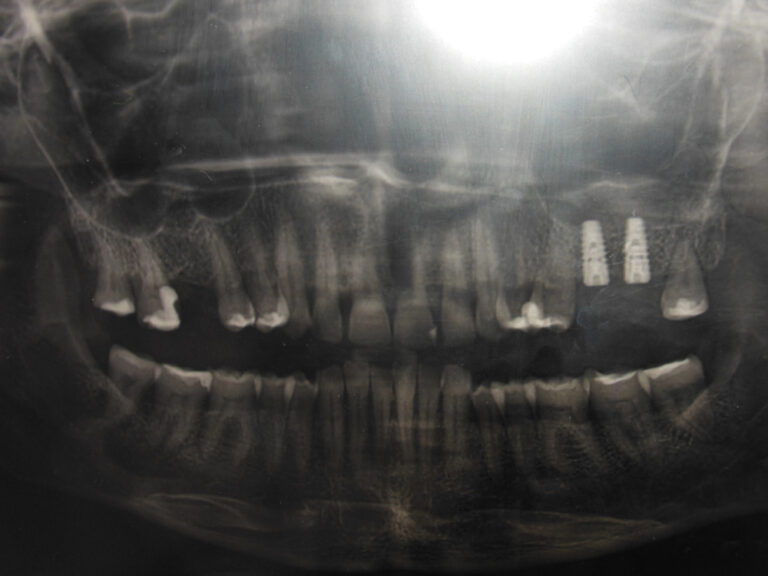

Implanty zygomatyczne

Przykłady implantologii